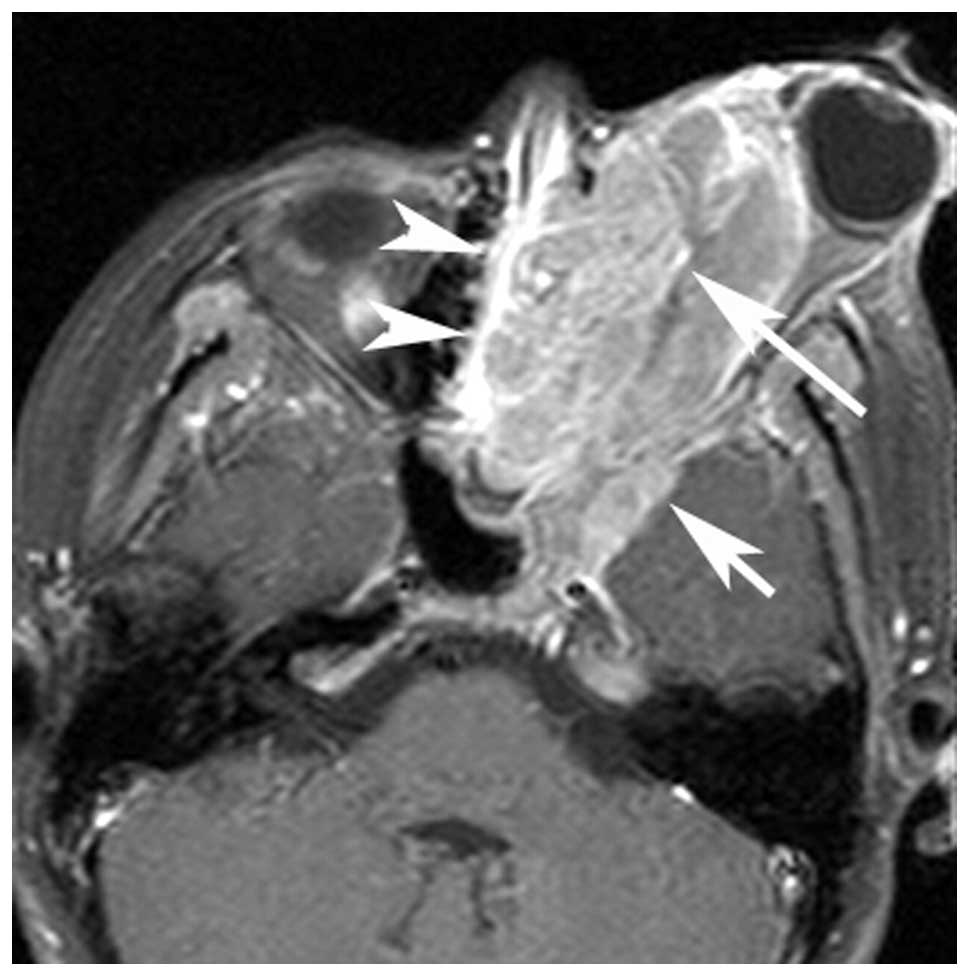

If you are looking for Parameningeal head and neck rhabdomyosarcoma. a Axial T1-W MR image in you've visit to the right place. We have 34 Images about Parameningeal head and neck rhabdomyosarcoma. a Axial T1-W MR image in like An Unusual Case of Alveolar Rhabdomyosarcoma of the Neck in an Adult, Non-parameningeal head and neck rhabdomyosarcoma. a Axial T1-W and also Non-parameningeal head and neck rhabdomyosarcoma. a Axial T1-W. Here you go:

Parameningeal Head And Neck Rhabdomyosarcoma. A Axial T1-W MR Image In

www.researchgate.net

www.researchgate.net

Non-parameningeal Head And Neck Rhabdomyosarcoma. A Axial T1-W

www.researchgate.net

www.researchgate.net

An Adult Spindle Cell Rhabdomyosarcoma In The Head And Neck Region With

jmedicalcasereports.biomedcentral.com

jmedicalcasereports.biomedcentral.com

rhabdomyosarcoma neck case spindle